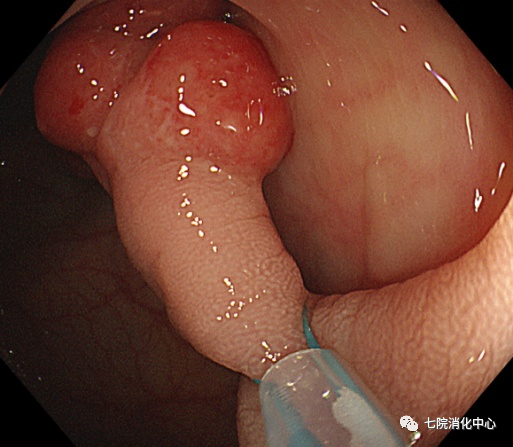

①热圈套器息肉切除术:基本原理是如果有足够的电流通过,产生的热量使细胞破裂导致组织被切割。对于小型息肉切除术,不建议热圈套器,因为它们有发生热不良事件的风险。建议热圈套器用于10~19mm带蒂息肉,因带蒂息肉的茎部具有穿透性血管,要求某种形式的预防止血。热圈套器息肉切除术引起的烧灼是防止立即出血的一种手段。

②冷圈套器:具有切除整个息肉的能力,避免了零碎的切除,并且可用于在同一过程中发现的较大息肉。其优点是可以防止电灼引起的对黏膜下血管组织的损害,并且对患者术后活动或饮食的限制较少。因为在冷圈套器息肉切除术期间不使用电灼,其术后出血和穿孔的发生率较低。